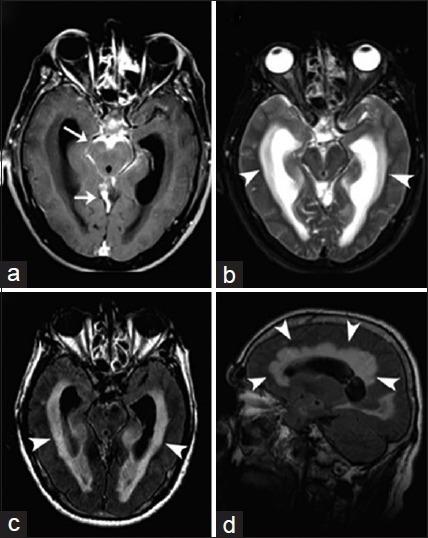

中枢神经系统真菌感染:图文综述

Fungal Infections of the Central Nervous System: A Pictorial Review.

Fungal infections of the central nervous system (CNS) pose a threat to especially immunocompromised patients and their development is primarily determined by the immune status of the host. With an increasing number of organ transplants, chemotherapy, and human immunodeficiency virus infections, the number of immunocompromised patients as susceptible hosts is growing and fungal infections of the CNS are more frequently encountered. They may result in meningitis, cerebritis, abscess formation, cryptococcoma, and meningeal vasculitis with rapid disease progression and often overlapping symptoms. Although radiological characteristics are often nonspecific, unique imaging patterns can be identified through computer tomography as a first imaging modality and further refined by magnetic resonance imaging. A rapid diagnosis and the institution of the appropriate therapy are crucial in helping prevent an often fatal outcome.

中枢神经系统(CNS)真菌感染对免疫功能低下的患者构成威胁,其发病主要取决于宿主的免疫状态。随着器官移植、化疗及人类免疫缺陷病毒感染病例的增多,作为易感宿主的免疫功能低下患者数量不断增加,中枢神经系统真菌感染也更为常见。它们可能导致脑膜炎、脑炎、脓肿形成、隐球菌瘤及脑膜血管炎,疾病进展迅速且症状常相互重叠。尽管影像学特征通常不具有特异性,但计算机断层扫描作为首选成像方式可识别出独特的影像模式,磁共振成像则可进一步完善。快速诊断并采取恰当治疗对于预防往往致命的后果至关重要。